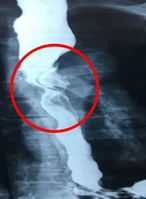

탐폰 사용과 피임 시술 중 어려움을 겪은 여성이 선천적 생식기 이상 진단을 받은 사례가 공개됐다.네덜란드 레이던대 메디컬센터 산부인과 의료진에 따르면, 10대 여성 한 명이 탐폰을 사용했다가 질 안에 걸려 응급실을 내원했다. 의료진은 기구로 제거를 시도했지만 실패했다. 이후 탐폰이 질 내부의 한 조직에 걸려 있다는 사실을 발견했고, 이후 ‘중격 처녀막’ 진단을 받았다. 중격 처녀막은 처녀막 가운데에 얇은 막이 하나 더 있어, 질 입구가 둘로 나뉘어 보이는 선천적 구조다.이후 환자는 몇 년간 무월경을 겪었다. 외부 생식기 구조는 정상이었고, 특별한 건강 이상이 발견되지 않았다. 과도한 운동으로 나타난 증상이라 판단했고, 운동 강도를 줄이자 생리가 자연스럽게 다시 시작됐다.하지만 몇 년 후 자궁내장치를 삽입하던 중 문제가 발견됐다. 자궁내장치가 자궁 한쪽에만 위치한 모습이 확인되면서 쌍각 자궁을 의심했고, 이후 자궁경 검사를 통해 선천적인 자궁 구조 이상이 있다는 사실이 발견됐다. 일반적인 자궁은 하나의 외형으로 이루어져 있지만, 쌍각 자궁은 두 개의 자궁이 합쳐지지 않은 상태를 말한다.의료진은 “처녀막 이상과 자궁 기형은 각각 따로 연구돼 왔지만, 실제로는 함께 나타나는 경우가 꽤 보고되고 있어 그 연관성도 제기되고 있다”며 “다만 그 원인은 아직 정확하게 밝혀지지 않았다”고 말했다. 이어 “처녀막 이상이 진단되면 자궁 등 내부 조직도 추가로 검사할 필요가 있다”고 했다. 자궁 기형을 놓치면 임신이나 시술 때 문제가 발생할 수 있다. 이 사례는 ‘큐레우스’ 저널에 26일 게재됐다.